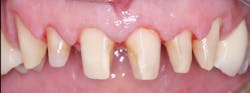

Figure 4: Patient with splinted anterior crowns and large carious lesion on lateral incisor had moderate constant pain

Figure 5: Patient had moderate postoperative pain after tooth preparation appointment.

Figure 6: Patient had almost no postoperative pain after tooth preparation appointment. Both patients in Figures 5 and 6 had same apparent trauma during tooth preparation, but they reported very dissimilar postoperative pain.